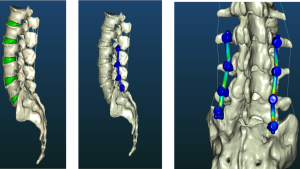

From Aerospace to Healthcare: How Digital Twin Technology is Transforming Spine Care

Digital twin technology has revolutionized industries like automotive and aerospace, enabling engineers to simulate, test, and optimize complex systems before real-world implementation. This innovation, pioneered by companies like MSC Software,

MDsim: transforming spine surgery through simulation technology

MDsim was founded by three visionary brothers—Richard, Dany, and Roger Assaker—each bringing a distinct set of skills to the table. Roger, a serial entrepreneur in simulation technology, Richard, a renowned